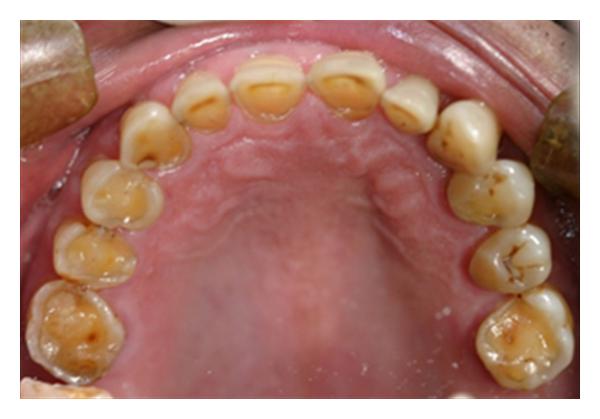

Another common sign of tooth erosion from acid reflux can be the yellowing of teeth. This is another sign that acids from your stomach are wearing away the enamel and slowly causing massive dental issues. If you are noticing a significant amount of yellowing around all of your teeth it could be an acid reflux issue as well. So what are some things you can do to help prevent these issues?